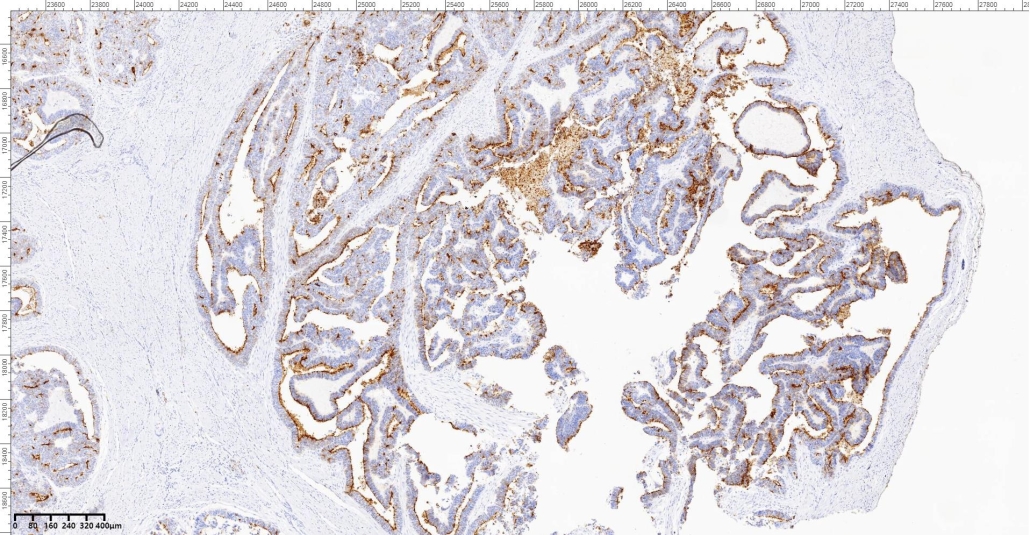

A 65-year- old female presented with vaginal bleeding. On radiological examination there was a diffuse thickening of endometrium. Patient underwent total abdominal hysterectomy and bilateral salpingo ophrectomy. On gross examination there was a grayish white mass involving the uterine cavity.